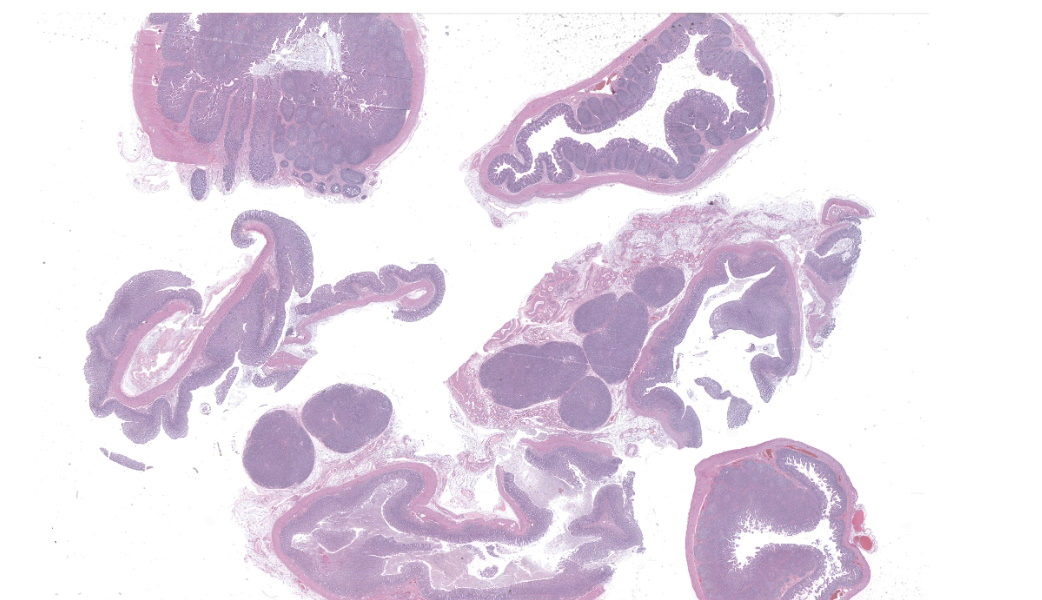

Microscopic Description:

Ileum: In several sections, there is moderate multifocal blunting and fusion of villi with a crypt: villus ratio of 1:1. Apical enterocytes are often moderately attenuated with loss of the brush border and reduced apical cytoplasm. In some sections, these cells have a profound number of intracellular but extracytoplasmic 1-2 um circular eosinophilic apicomplexan organisms with 0.5 um basophilic nuclei (Cryptosporidium sp.). In other sections, these cells contain numerous larger apicomplexans with varied life-stages apparent including: 10 x 5 um curvilinear binucleate meronts (type I meronts), 4 x 12 um curvilinear uninucleate merozoites (type I merozoites), 9 x 6 um ovoid multinucleate meronts (type II meronts), multiple 3 x 12 um curvilinear uninucleate merozoites joined at their base by a residual body (type II merozoites), a 12um diameter circular lightly basophilic microgamont filled with numerous peripheral uninucleate deeply basophilic microgametes, or a 18 um diameter circular lightly basophilic macrogamont with a 8 um granular circular nucleus (macrogamont) (Cystoisospora suis). Rare crypts are ectatic, lined by moderately flattened, attenuated epithelium, and filled with cellular and karyorrhectic debris admixed with rare degenerate neutrophils (crypt abscesses). The associated lamina propria is often infiltrated by numerous eosinophils admixed with a few neutrophils. In one section, there is profound necrosis in Peyer’s patches, characterized by abundant karyorrhectic and cellular debris admixed with rare neutrophils, that often obscures typical follicular architecture. Similar changes are occasionally present in the overlying lamina propria, with marked lymphocytolysis and loss of proprial architecture. Vascular structures in all tunics are moderately congested, and macrophages occasionally aggregate around medium-caliber vessels in the submucosa.Spiral Colon: In both sections, there is moderate multifocal ulceration of the colonic mucosa characterized by loss of apical colonocytes with abundant cellular and karyorrhectic debris admixed with minimal fibrin and extravasated erythrocytes adhered to the exposed lamina propria. Adjacent colonocytes are often flattened, irregularly spaced, with reduced apical cytoplasm (attenuation). The associated lamina propria is often infiltrated by neutrophils and eosinophils admixed with necrotic debris and a few macrophages. Crypts within these areas are often ectatic, lined by mildly attenuated epithelium, and filled with either cellular and karyorrhectic debris admixed with degenerate neutrophils (crypt abscesses) or numerous eosinophils. Several other crypts are filled with up to 15 5 x 7 um pyriform to crescent-shaped protozoa with lightly basophilic cytoplasm and a faint nucleus (Suspect Trichomonads). The colonic lumen contains abundant cellular debris admixed with numerous colonies of basophilic bacteria with morphology ranging from coccoid to bacillary to filamentous, as well as rare 80 um circular flagellated protozoa with a prominent bean-shaped nucleus and a large cytoplasmic vacuole and abundant phagocytosed cellular debris (Suspect Balantidium coli). The submucosa is multifocally infiltrated by numerous macrophages admixed with lymphocytes and a small amount of karyorrhectic debris and these cells often aggregate around medium to large caliber vessels. Multifocally the cortical and medullary architecture of the mesenteric lymph node is effaced by abundant cellular and karyorrhectic debris (lymphocytolysis) admixed with rare infiltrating neutrophils and macrophages.

Contributor's Morphologic Diagnoses:

Ileum and colon (mediastinal lymph node, Peyer’s patches, and lamina propria): Lymphoid necrosis, multifocal, profound, subacute.Ileum: Atrophic enteritis, necrosuppurative and eosinophilic segmental, marked, subacute, with crypt abscesses and numerous intralesional apicomplexans with morphology consistent with Cryptosporidium spp. and Cystoisospora suis

Colon: Ulcerative colitis, segmental, marked, subacute, with crypt abscesses and numerous intralesional protozoans with morphology consistent with Balantidium coli, and Trichomonads.